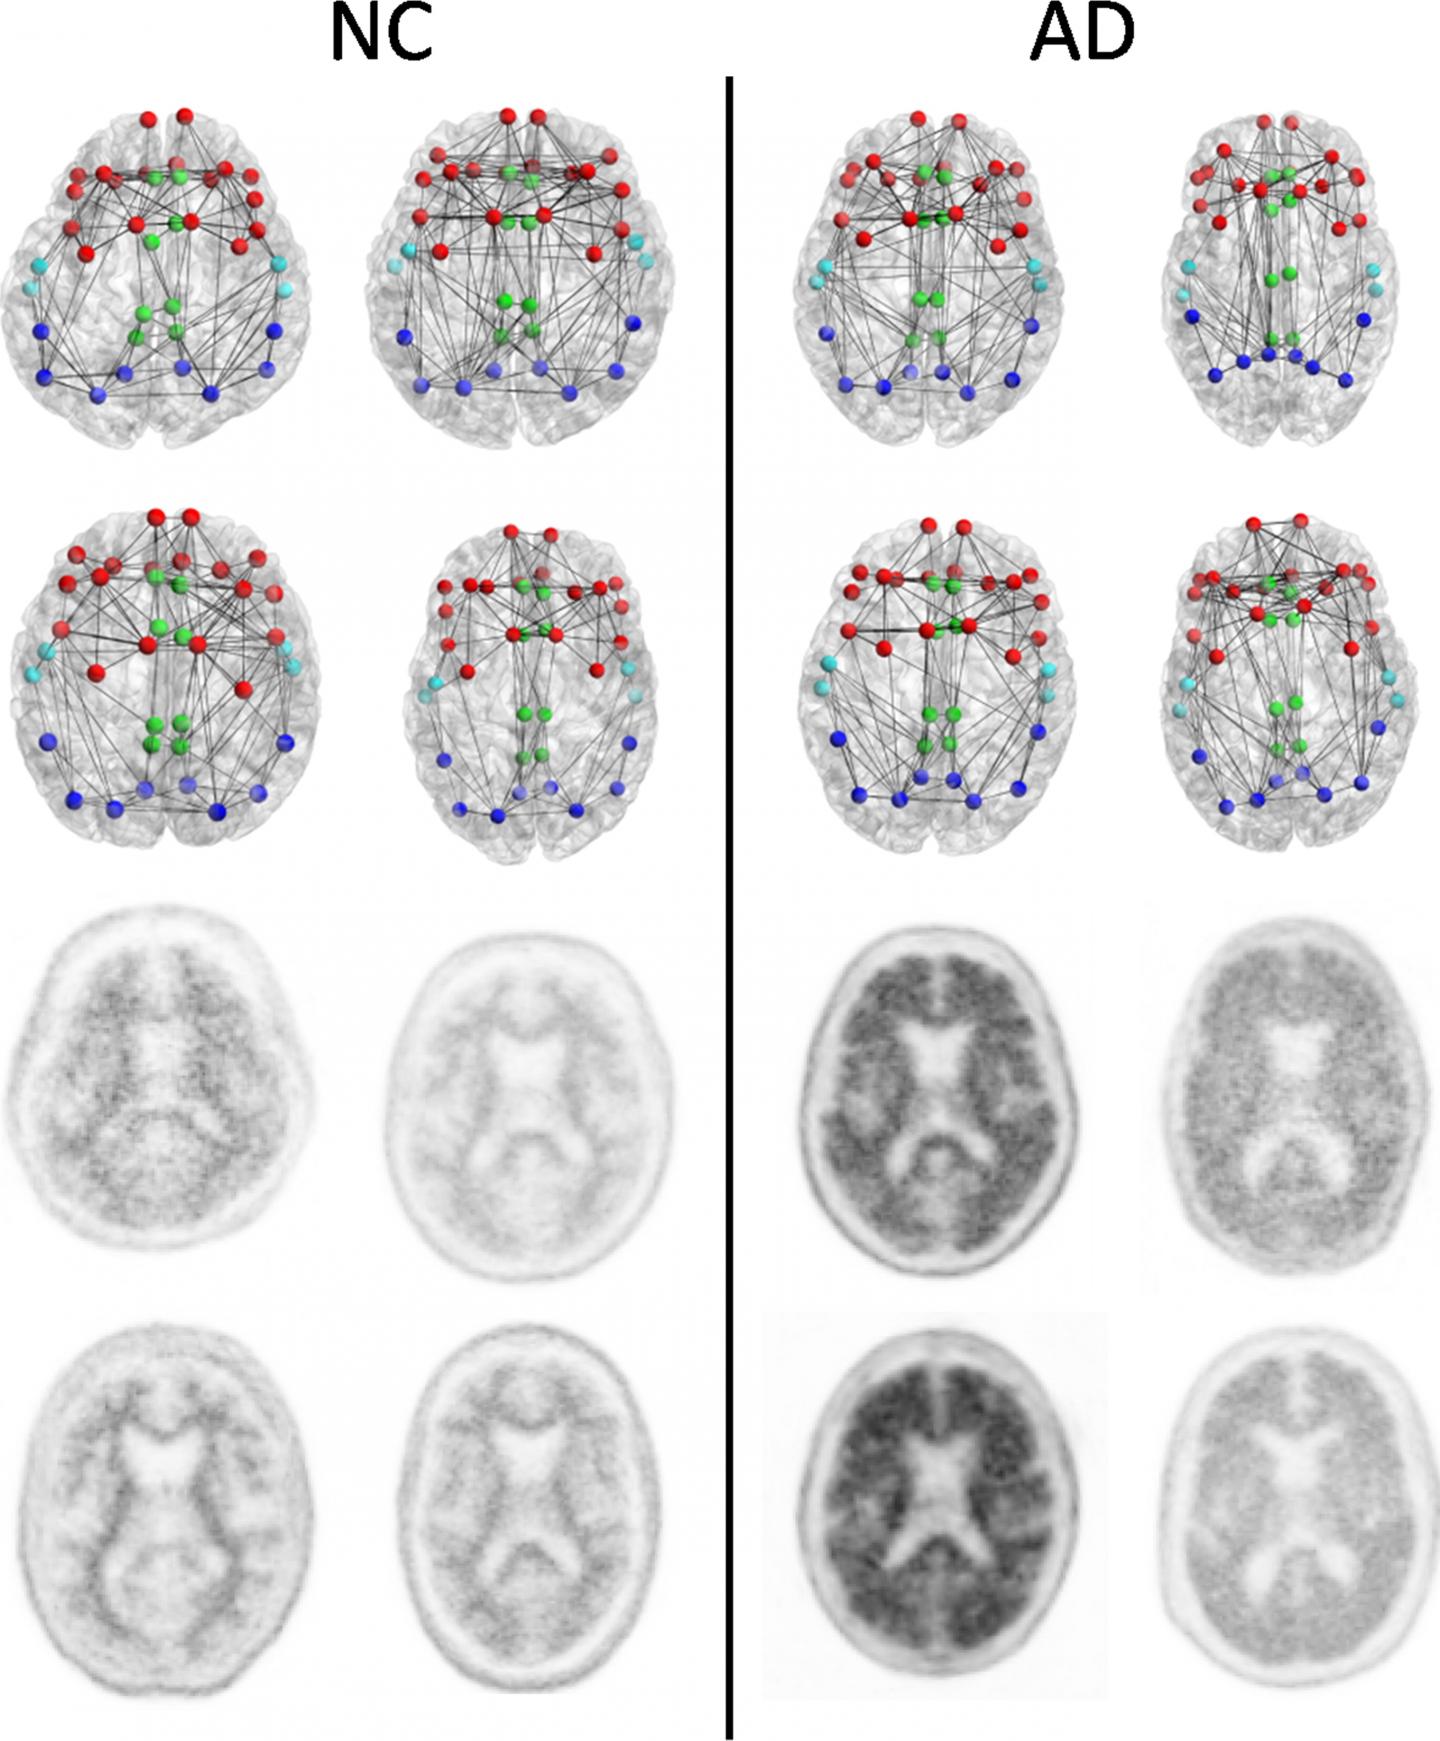

Connettomi strutturali (prime due righe) e corrispondenti immagini PET florbetapir (ultime due righe) di 4 pazienti con cognizione normale (NC) con onere amiloide nell'intera corteccia molto basso (a sinistra) e 4 pazienti con AD con l'onere di amiloide dell'intera corteccia più alto (a destra) concentrati sulle regioni composite usate nel connettoma vs l'analisi amiloide. I nodi rappresentano i baricentri delle parcellazioni Freesurfer dei lobi frontale (rosso), cingolato (verde), temporale (azzurro) e parietali (blu scuro). Questo è solo uno schema destinato a mostrare i concetti e non intende mostrare alcuna differenza generalizzabile e visivamente distinguibile tra i pazienti con NC e quelli con AD. Le metriche di rete strutturali forniscono informazioni più sensibili sul connettoma che sono evidenti solo con la scansione. (Fonte: RSNA) Clicca per ingrandire.

Per il nuovo studio, i ricercatori hanno esaminato il [[Connettoma]] strutturale del cervello, una mappa di tratti di sostanza bianca che trasportano i segnali tra le diverse aree del cervello. "Il Connettoma strutturale ci fornisce un modo per caratterizzare e misurare queste connessioni e come cambiano nelle malattie o nell'invecchiamento", ha detto il co-autore Jeffrey W. Prescott, MD, Ph.D., radiologo del Medical Center della Duke University di Durham in Nord Carolina.

I ricercatori hanno correlato i cambiamenti nel Connettoma strutturale con i risultati di scansioni a tomografia ad emissione di positroni (PET) con florbetapir, una tecnica che misura la quantità di placche di amiloide-beta nel cervello. Un maggior assorbimento di florbetapir corrisponde ad una maggiore quantità di proteina.

I risultati hanno evidenziato una forte associazione tra assorbimento di florbetapir e cali nella forza del Connettoma strutturale in ciascuna delle cinque aree studiate del cervello. "Questo studio lega insieme due dei maggiori cambiamenti nel cervello di Alzheimer (cambiamenti strutturali del tessuto e deposizione patologica di placca amiloide) e suggerisce un ruolo promettente per la DTI come possibile elemento diagnostico aggiuntivo", ha detto il dottor Prescott.

Sulla base di questi risultati, la DTI può avere un ruolo nella valutazione dei danni cerebrali all'inizio dell'Alzheimer e per il monitoraggio dell'effetto di nuove terapie. "Si ritiene di norma che l'Alzheimer eserciti i suoi effetti sul pensiero attraverso i danni alla materia grigia del cervello, dove è concentrata la maggior parte delle cellule nervose", ha detto Jeffrey R. Petrella, MD, professore di radiologia alla Duke e autore senior dello studio. "Questo studio suggerisce che la deposizione di amiloide nella materia grigia colpisce i collegamenti associati nella sostanza bianca, che sono essenziali per condurre i messaggi attraverso i miliardi di cellule nervose nel cervello, rendendo possibili tutti gli aspetti delle funzioni mentali".